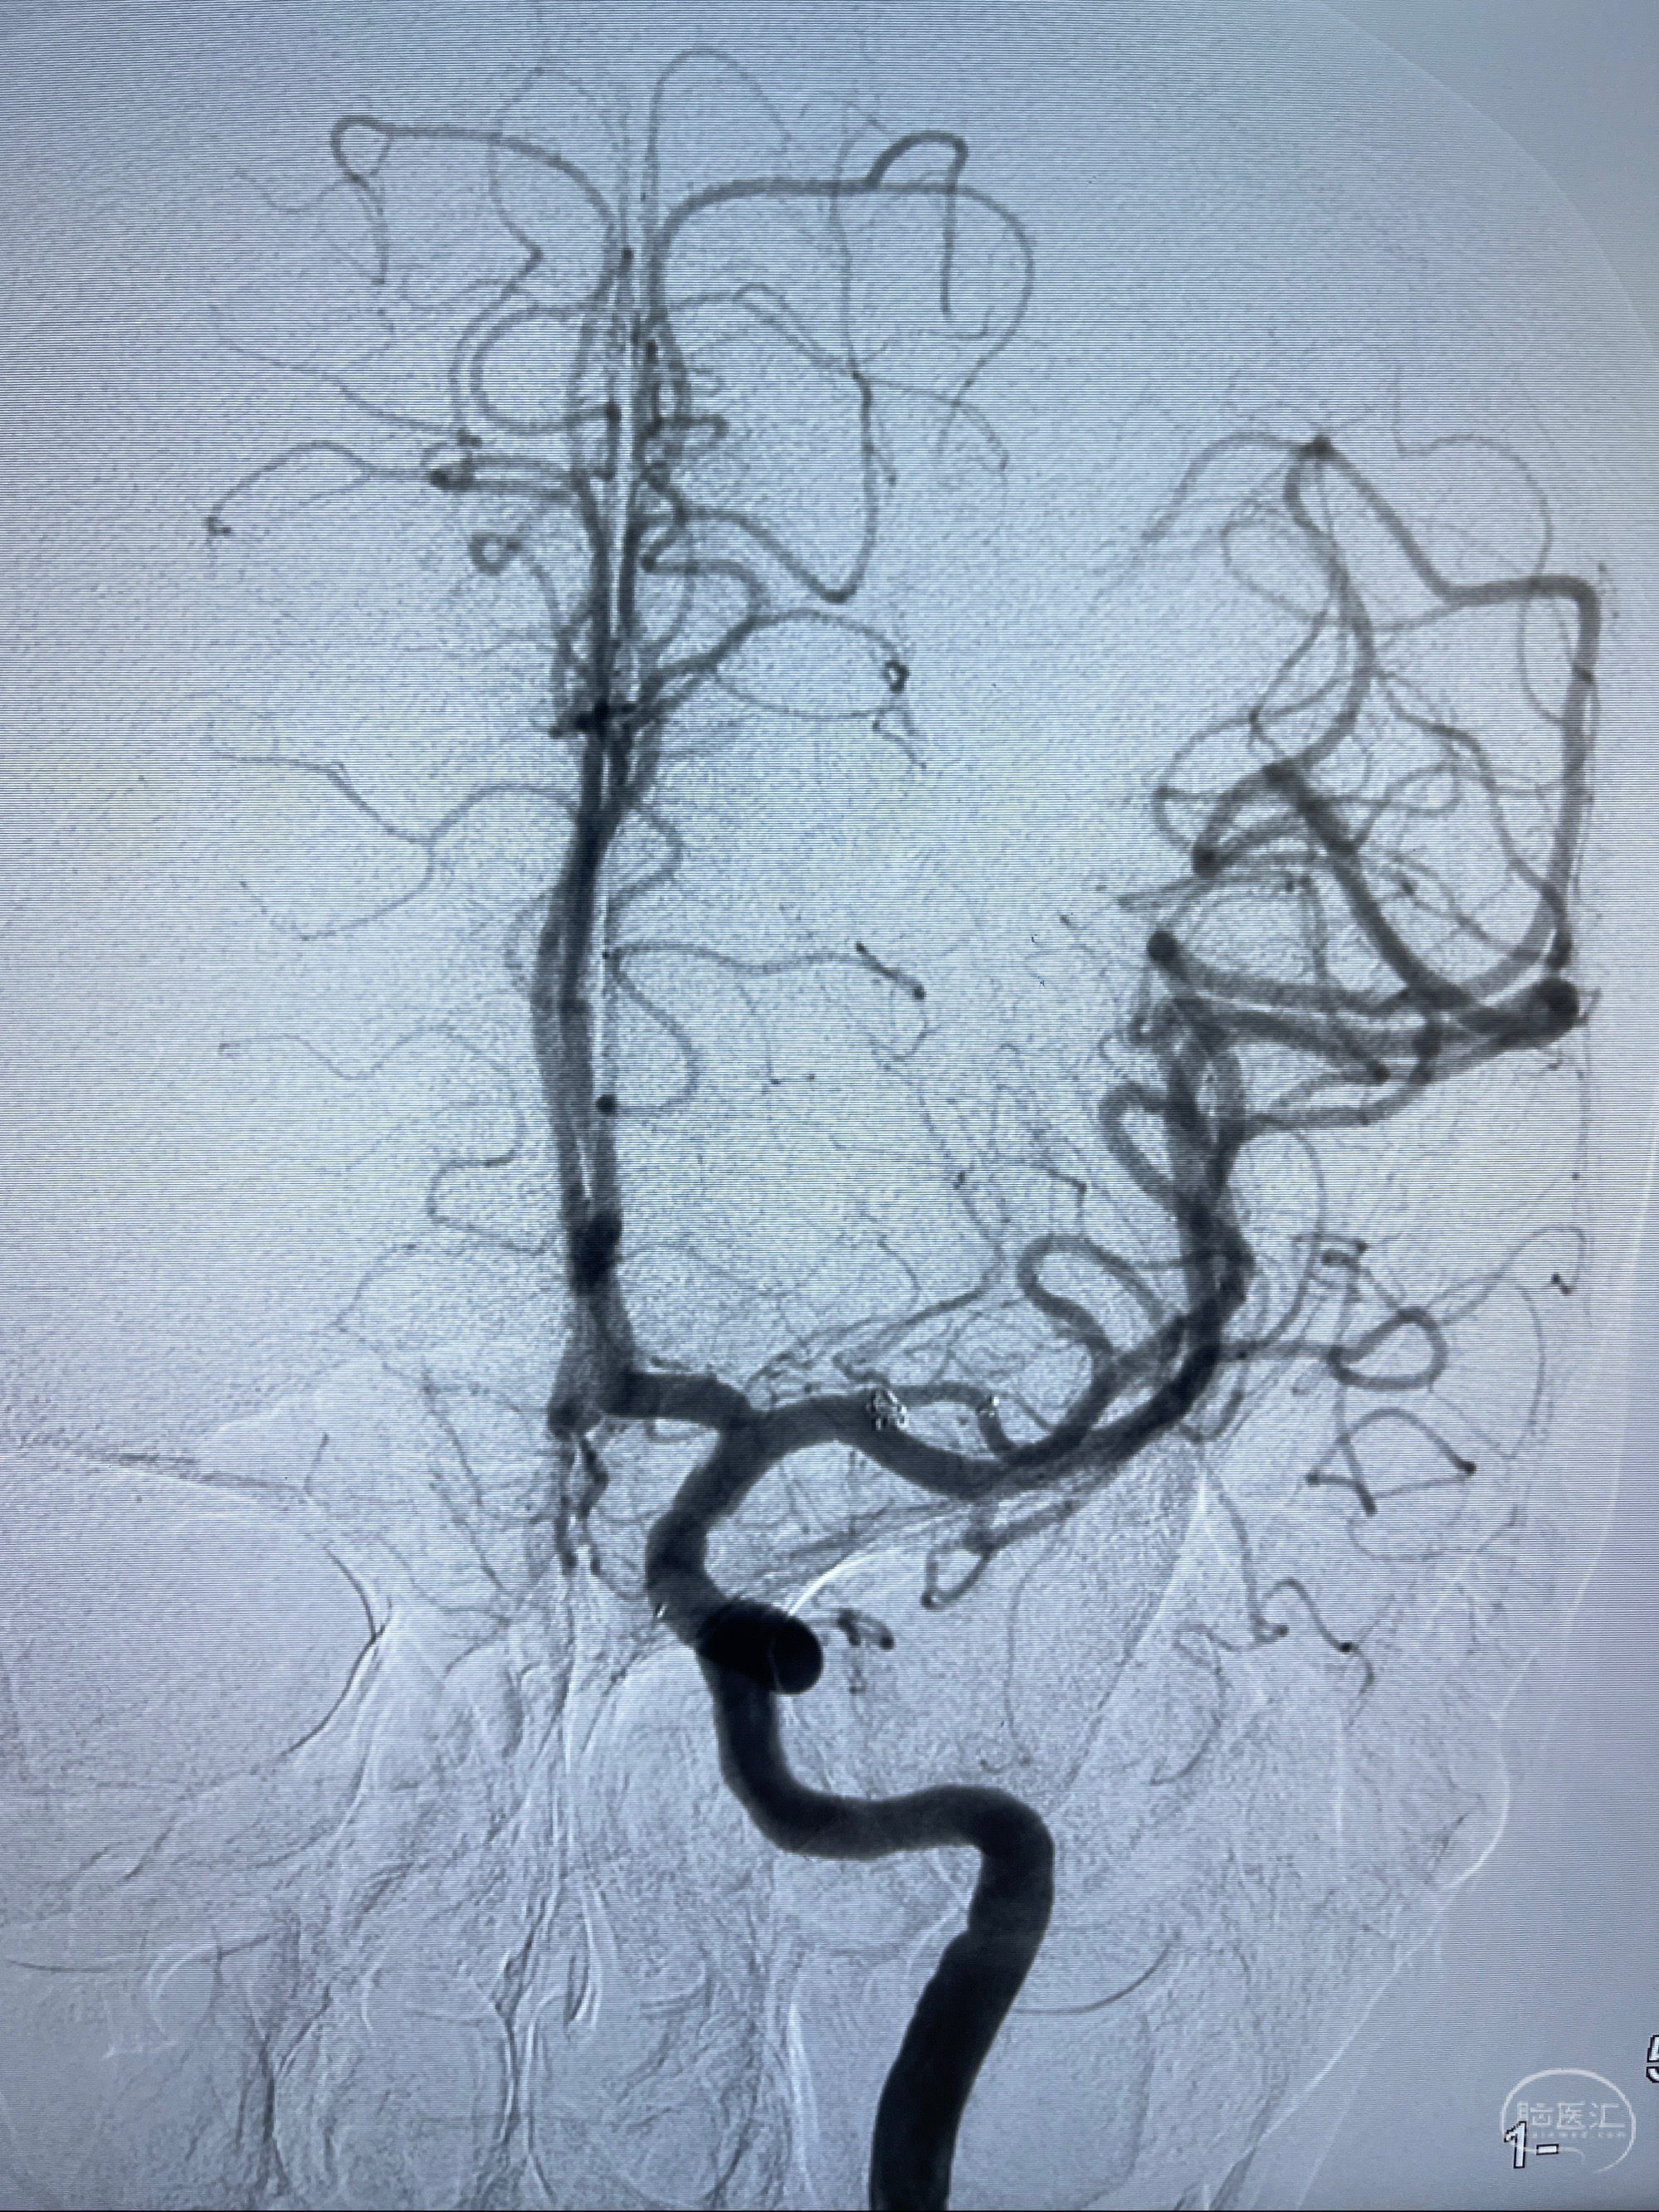

2023-08-14DSA:

左侧大脑中动脉动脉瘤,约2.6-2.8-3.4-2mm大小(瘤颈部、瘤体部、瘤高)